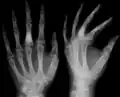

X-ray showing enchondromas localized in the lower part of the radius of a 37-year-old patient affected with Ollier disease